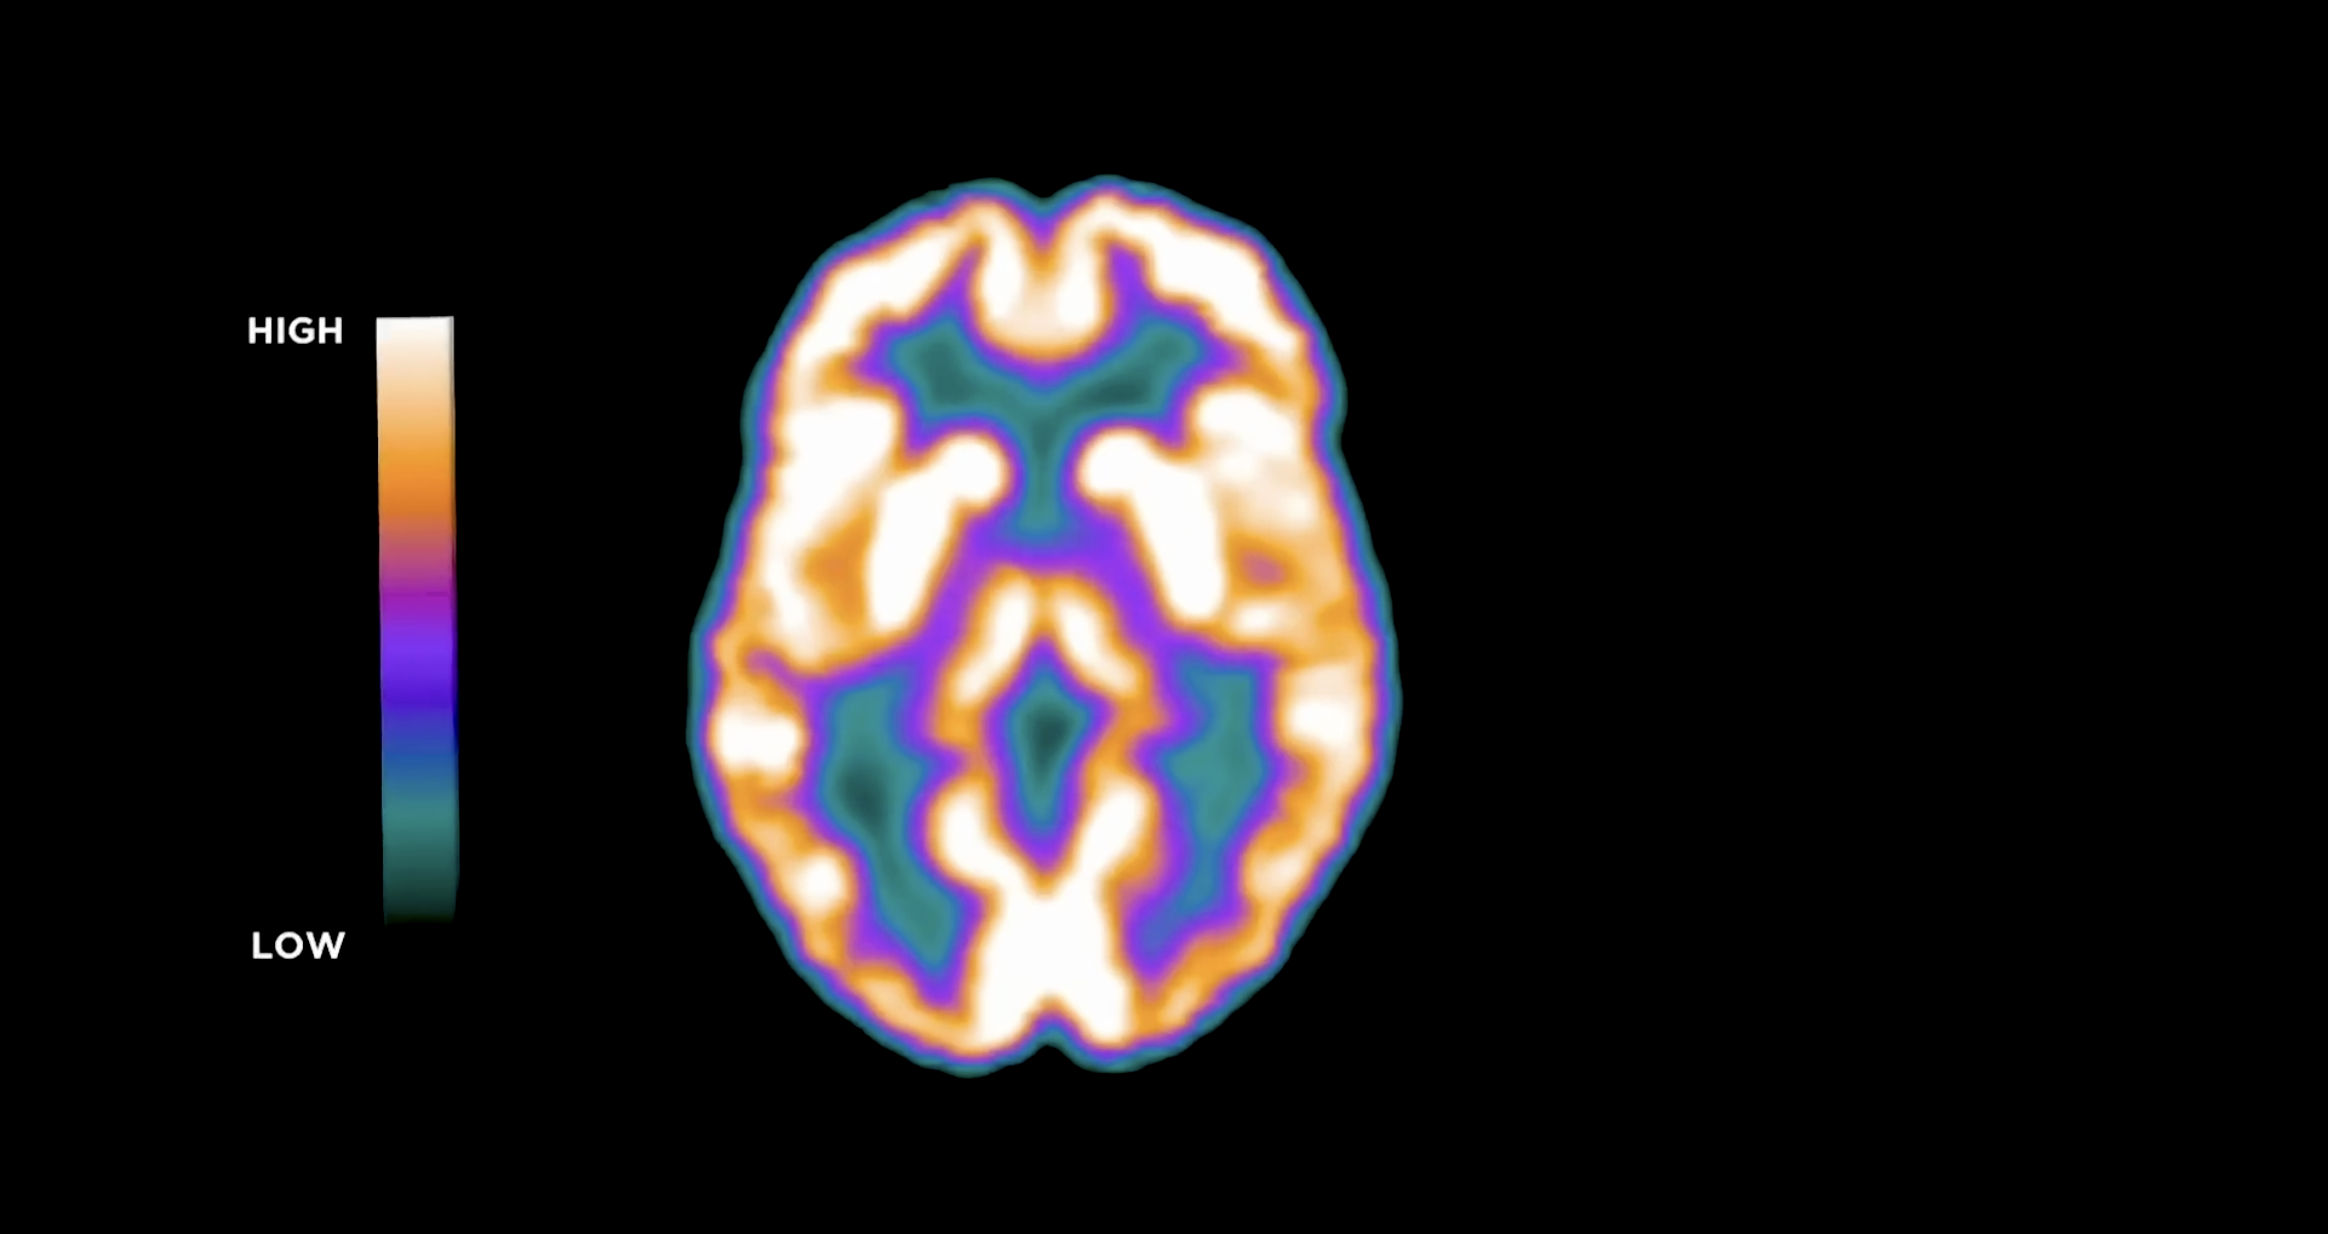

Alzheimer’s disease is often framed as the unavoidable consequence of growing old — a condition that simply arrives with time. But that explanation, while convenient, tells only part of the story. Women account for nearly two-thirds of Alzheimer’s cases, a disparity commonly attributed to longer life expectancy. Longevity certainly plays a role, yet it does not fully explain why the burden of the disease falls so heavily on women.

Increasingly, researchers are looking earlier in life for answers. Alzheimer’s is now understood as a disease that develops slowly over decades, long before memory problems appear. In fact, the biological groundwork for cognitive decline may begin in midlife — or even earlier — as subtle changes accumulate in brain metabolism, vascular health, and cellular resilience. As one neuroscientist put it, the disease that ultimately emerges in our seventies may have begun quietly in our thirties.

For women, one of the most significant biological transitions occurs during perimenopause and menopause. As estrogen levels fluctuate and eventually decline, the brain undergoes measurable changes in energy use, temperature regulation, sleep patterns, and cellular signaling. These shifts do not cause Alzheimer’s on their own. But they may influence whether the brain becomes more resilient — or more vulnerable — to the processes that drive neurodegeneration.

If Alzheimer’s unfolds over decades rather than years, then midlife may be where the story meaningfully begins. Understanding what happens in the brain during this period — particularly for women — may be one of the most important frontiers in preventing the disease long before its symptoms appear.